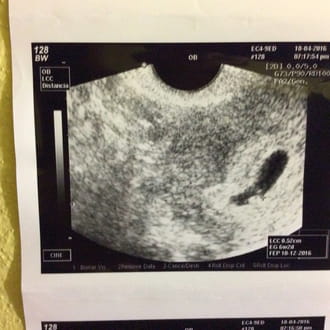

Hola por favor necesito su ayuda el día 30 de marzo me tenia que bajar si me bajo pero sólo una pequeña mancha y en menos de dos horas ya no sangraba ...